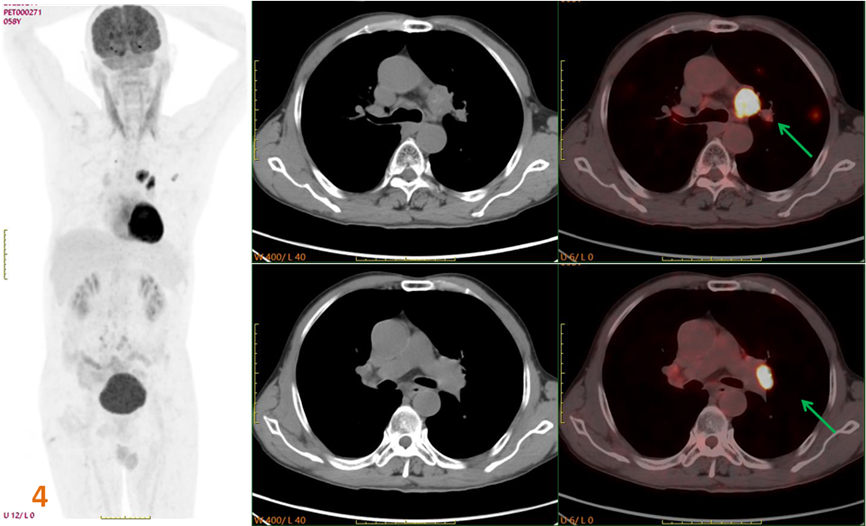

為明確原發(fā)灶行PET-CT進(jìn)一步檢查(圖3、4)。PET/CT示:左肺上葉不規(guī)則囊性灶(SUVmax約5.3),左肺門、主動脈弓下高代謝病變(SUVmax約12.1);診斷為左肺上葉癌并多發(fā)轉(zhuǎn)移。

圖3、4. 左肺上葉不規(guī)則囊性灶(黃箭),SUVmax約5.3;左肺門、主動脈弓下高代謝病變(綠箭)SUVmax約12.1。